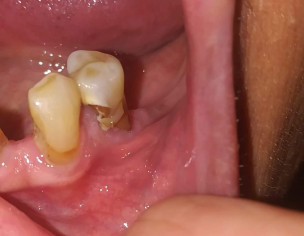

my mother is diabetic. And she uses dentures. Her denture had been a little tight for her for the past month and around ten days ago she started having severe pain in the tooth on which the denture sits. After a week of pain she developed a swelling around the tooth which is visible under the jaw and was tender to touch. She started on Augmentin 625 mg twice a day. It's fourth day. The swelling is not tender to touch anymore. The intensity of pain has decreased but she still gets bouts of pain for which panadol is providing temporary relief. As she is diabetic, hypertensive and also asthmatic, due to covid, we don't want her to go to dentist unless absolutely needed. Please guide if she absolutely has to visit the dentist or can this be managed at home with antibiotics or some other medication?

The tooth prognosis is not good. Patient ridge has resorbed (gum recession) and also root caries seen. We will check clinically the tooth mobility but as per picture the tooth needs to get extract after that the infection will subside and the swelling will get reduce. If patient is medically compromised doesn't matter it can be manage according to respective medical issues. If pain got relief with medication that's good, complete patients antibiotic course for 3 more days (as per 7 days course) and take pain killer (panadol) as needed. These medicines are safe for diabetic, hypertensive and asthmatic patients. So no need to visit dentist until it is manageable with medicines and yes if pain got unbearable and is not relieving with any medicines then you should visit to clinic. Thank you